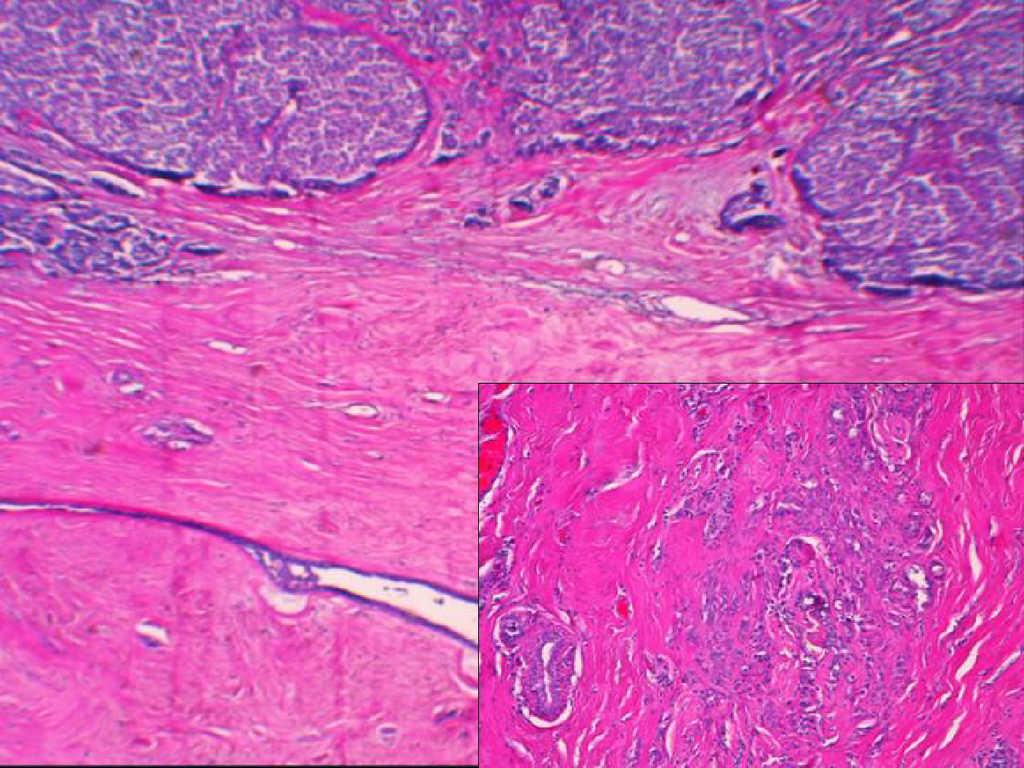

Caso 2Mujer de 46 años, sin antecedentes de interés, que fue remitida a nuestra consulta para la evaluación de un nódulo no palpable a las doce de la mama izquierda. Esta lesión había sido seguida durante más de 20 años, pero había presentado cambios mamográficos compatibles con malignidad. Durante la exploración física no se palparon lesiones ni adenopatías axilares. La punción aspirativa con aguja fina señaló malignidad, por lo que se procedió a la biopsia estereotáctica guiada por arpón. El estudio anatomopatológico reveló un carcinoma ductal in situ tipo comedocarcinoma de 0,8cm en el interior de un fibroadenoma de 1cm de diámetro (figura 1). Los márgenes de resección estaban afectados, por lo que se reintervino para ampliarlos y realizar la biopsia selectiva del ganglio centinela (BSGC). El estudio histológico no demostró tumor residual y el ganglio centinela fue negativo para malignidad.

Figura 1. Caso 2. Aspecto intracanalicular típico de un fibroadenoma con carcinoma ductal in situ en el interior de la estroma hialinizada intralobulillar. Se aprecia el tipo comedocarcinoma en el componente epitelial (H-E, ×10 y ×40).